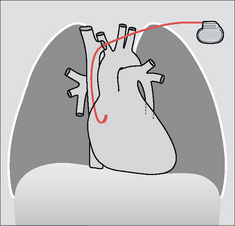

Some pacemakers have three electrodes: one in the right atrium, a second in the right ventricle, and a third lead is placed in the coronary sinus (Fig. 12.2). The coronary sinus lead paces the left ventricle. This system is referred to as biventricular pacing.

image

Figure 12.2 The position of the coronary sinus opening (red) into the right atrium. The sinus is approximately 3 cm long and runs in the AV groove on the posterior border of the heart. The coronary sinus is the vessel which transmits most of the venous drainage of the myocardium. The site of the foramen ovale is shown in blue.